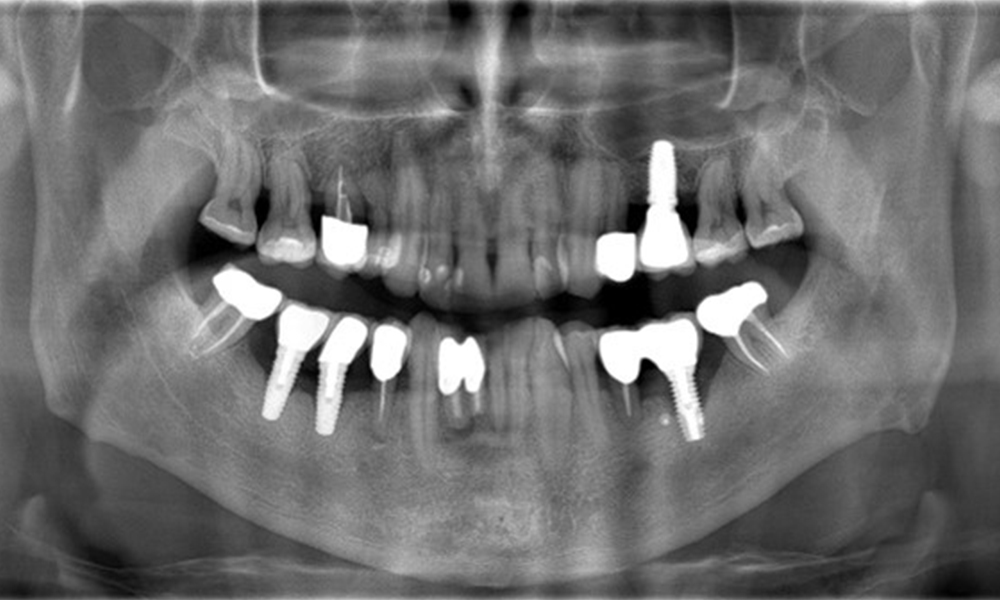

The X-ray images show the progression of bone loss.

The X-ray images show the progression of bone loss. OPG from 29.06.2020 (left) and OPG from 26.02.2024 (right).

The X-ray images show the progression of bone loss in the area of the implant in region 36: dental film from 11.02.2021 (left) and dental film from 18.01.2024 (right).